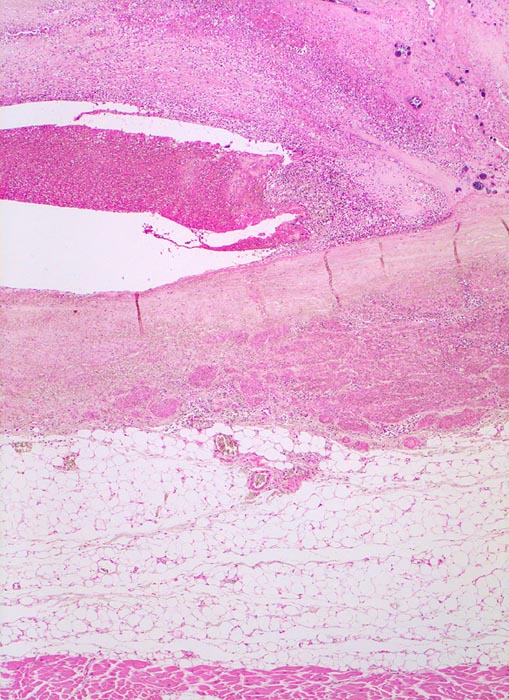

PathoPic – image database / PathoPic ID 4536 - Endocarditis ulcero-polyposa der Aortenklappe

Endocarditis ulcero-polyposa der Aortenklappe

Entzündung infektiös

Aortenklappe

Kardiovaskuläres System

Akut einsetzendes Krankheitsbild mit Fieber, Schüttelfrost, Müdigkeit und Dyspnoe. Blutkulturen wiederholt positiv für Staphylokokkus aureus. Keine Klappenvorschädigung bekannt.

Histologie

25